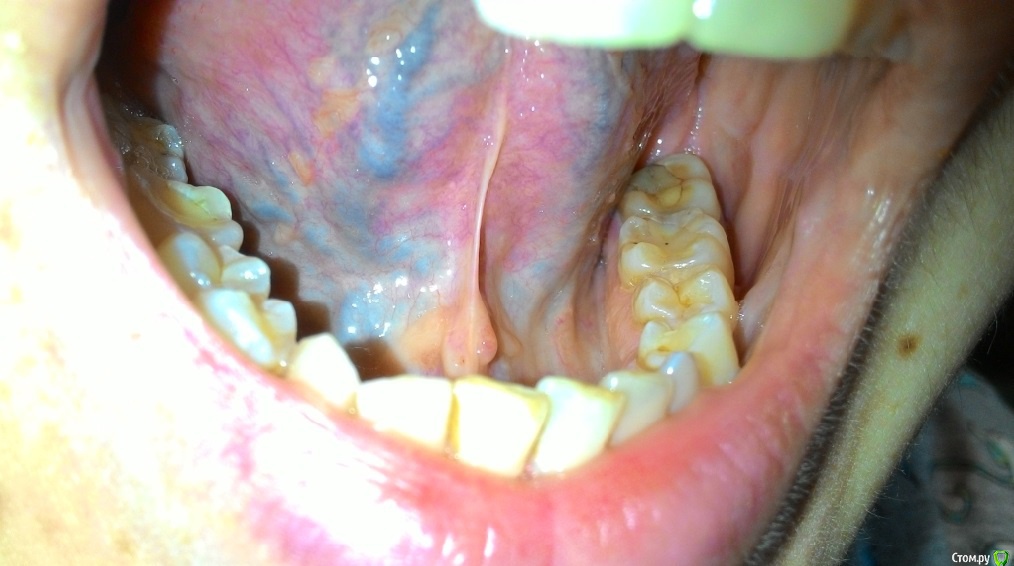

Пузырьки на уздечке под языком

На уздечке под языком у меня образовалось 2 пузырька.

28 декабря почувствовала, что как будто под языком что-то есть и оно мешается. Увидела эти пузырьки. Не болят.

29 декабря поехала снимать швы. Снимал другая доктор (мой был уже в отпуске), показала ей эти пузырьки, она сказала, что на вид пока не страшно, но что это - ей не понятно. Она показала меня еще другому доктору, та тоже сказала, что ничего страшного не видит, но толком не понимает, что это, порекомендовала наблюдать.

03 января - пузырьки сохраняются.